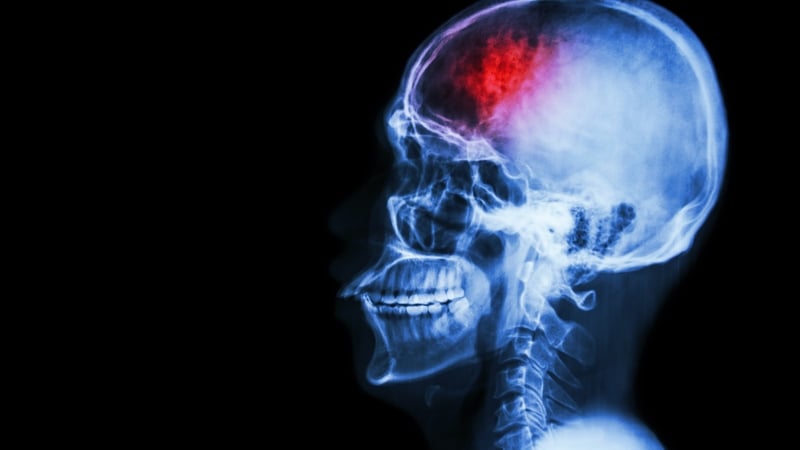

Stroke is a largely preventable condition and we could all be working towards reducing our chances of having a stroke. A stroke is caused by a disruption in blood flow to the brain from either a clot (ischemic stroke) or a brain bleed when a  blood vessel bursts (haemorrhagic). Both of these prevent blood from reaching all aspects of the brain and starves our brains of essential oxygen which results in our brain cells-neurons dying.

Acting quickly once you realise someone is having a stroke is very important as the average stroke kills two million brain cells every minute. The more neuron death, the more severe the affects of stroke can be. The exact symptoms and severity of the stroke will depend on the location of the stroke in the brain, the size of the stroke and the speed of treatment.